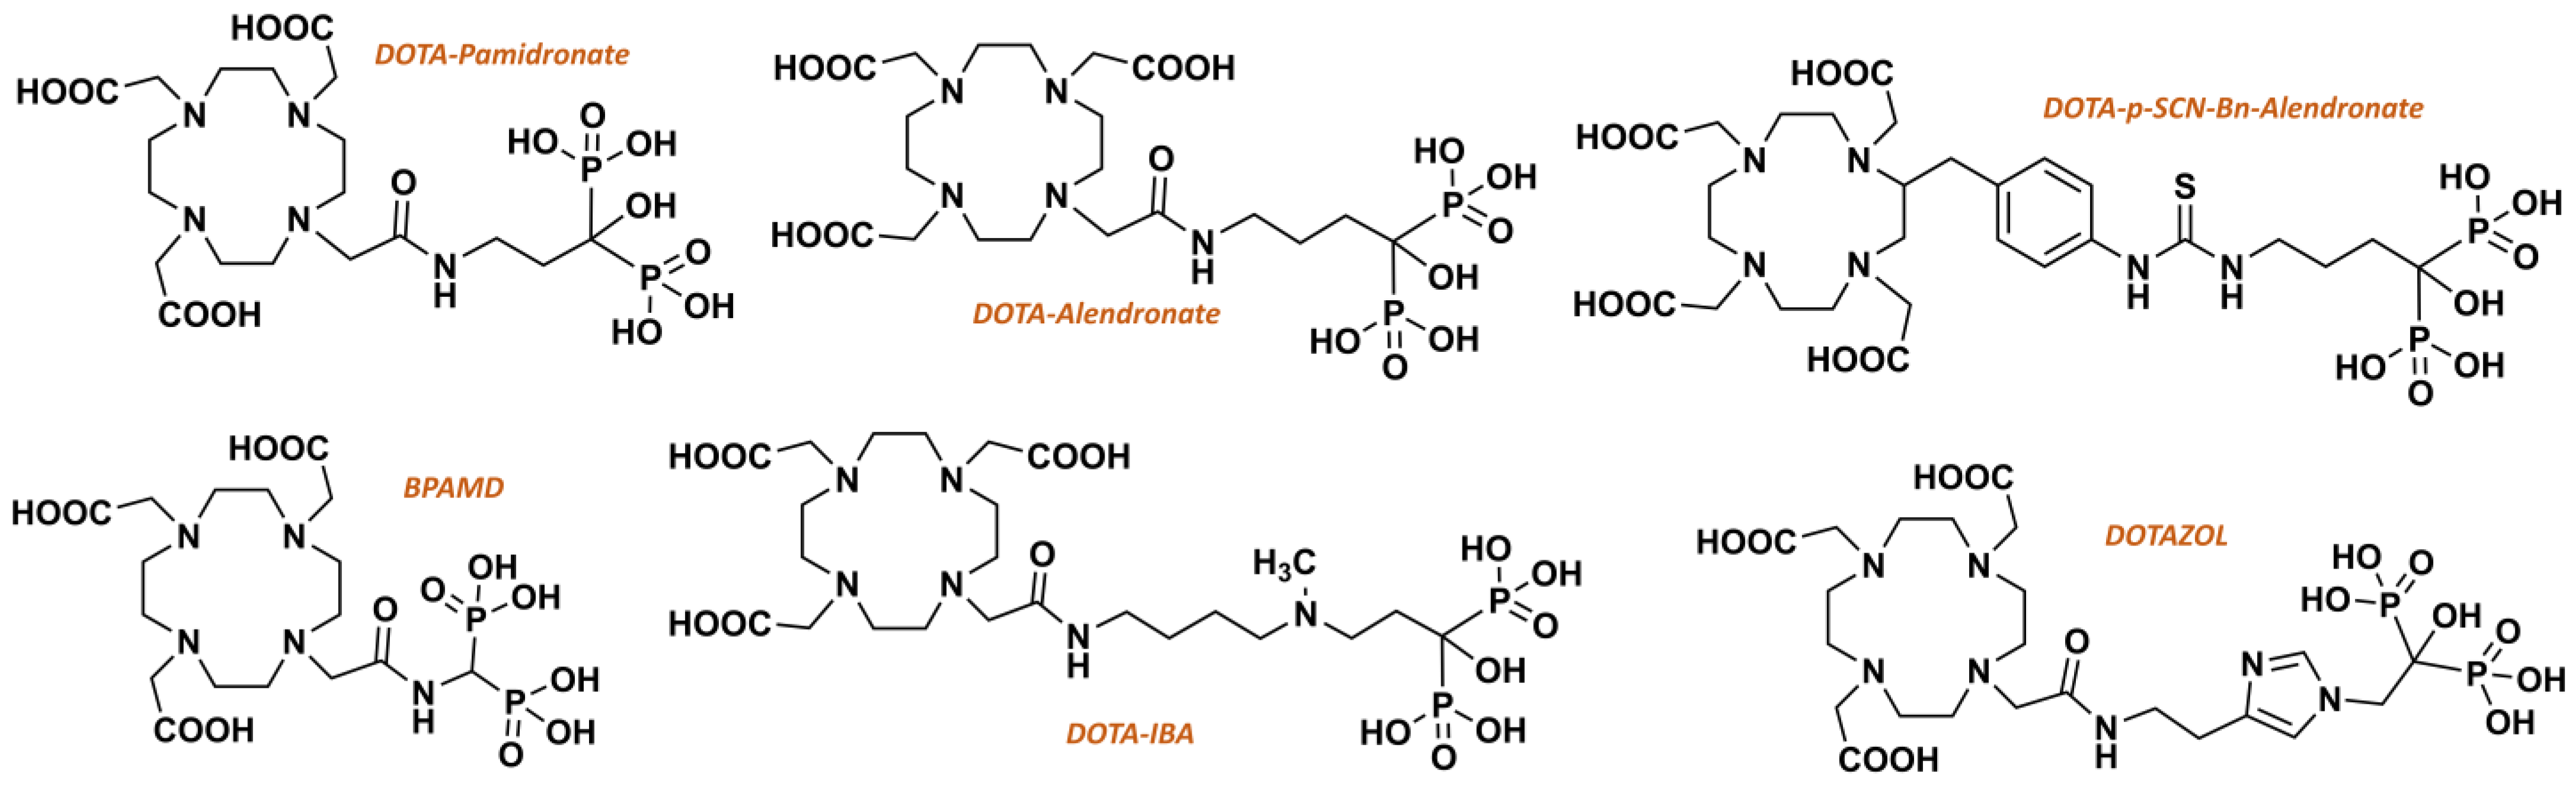

3.1. Chemical Synthesis of DOTAZOL